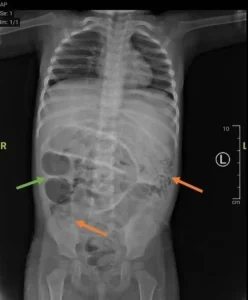

Κατά τη διάρκεια της χειρουργικής επέμβασης, οι γιατροί εντόπισαν και αφαίρεσαν πολυάριθμα σκουλήκια τύπου Ascaris lumbricoides, μήκους αρκετών εκατοστών, τα οποία είχαν δημιουργήσει «κυκλοφοριακή συμφόρηση» στο λεπτό έντερο του παιδιού.

Η τομή που πραγματοποιήθηκε για την αφαίρεση των παρασίτων έγινε σε σημείο περίπου 50 εκατοστά από το παχύ έντερο. Το έντερο στη συνέχεια συρράφτηκε και τα σκουλήκια στάλθηκαν για περαιτέρω ανάλυση σε εργαστήριο.